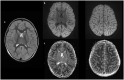

Pediatric Encephalopathy and Complex Febrile Seizures